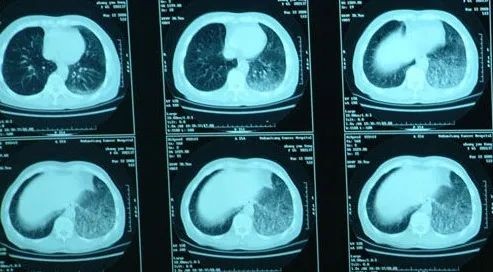

肺纖維化,簡單來說,就是肺部的正常組織逐漸被纖維瘢痕組織取代。想象一下,原本柔軟、富有彈性,如同海綿般能自如伸縮進行氣體交換的肺部,慢慢布滿了像絲瓜瓤一樣硬邦邦、沒有彈性的瘢痕。這可不是什么小問題,一旦肺部纖維化程度加深,患者會明顯感到呼吸困難,原本輕松就能完成的日?;顒?,如爬樓梯、快走,都可能變得氣喘吁吁。除了嚴重影響生活質量外,它甚至還會大幅縮短患者的生存周期,堪稱肺部健康的 “隱形殺手”。

(圖片來源:百度圖片)